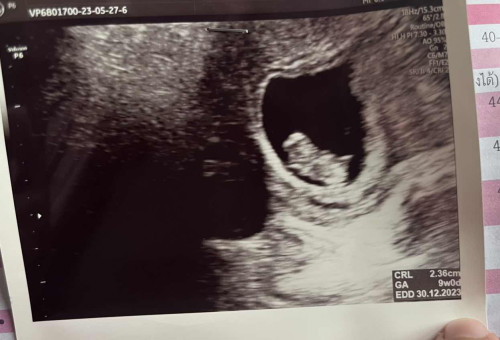

ขอดูรูปอุลตร้าซาวด์ของแม่ๆอายุครรภ์ 9-10 สัปดาห์หน่อยได้ไหมคะ

เห็นเป็นรูปเป็นร่างชัดเจนไหมคะ บ้านนี้รู้สึกเหมือนจะรูปร่างแปลกๆไหมคะ แต่หมอก็ไม่ได้บอกอะไร

9สัปดาห์1วัน จ้า